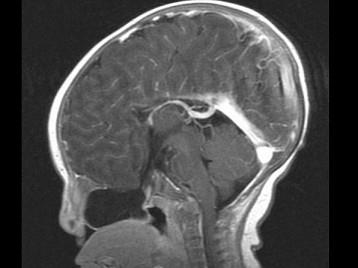

问题 两个月女婴,口咽部有一肿块,行CT检查如图,请选择最可能的诊断 ( )

选项 A、前脑无裂畸形 B、Dandy-Walker综合征 C、胼胝体发育不全 D、透明隔囊肿 E、脑积水

答案 C